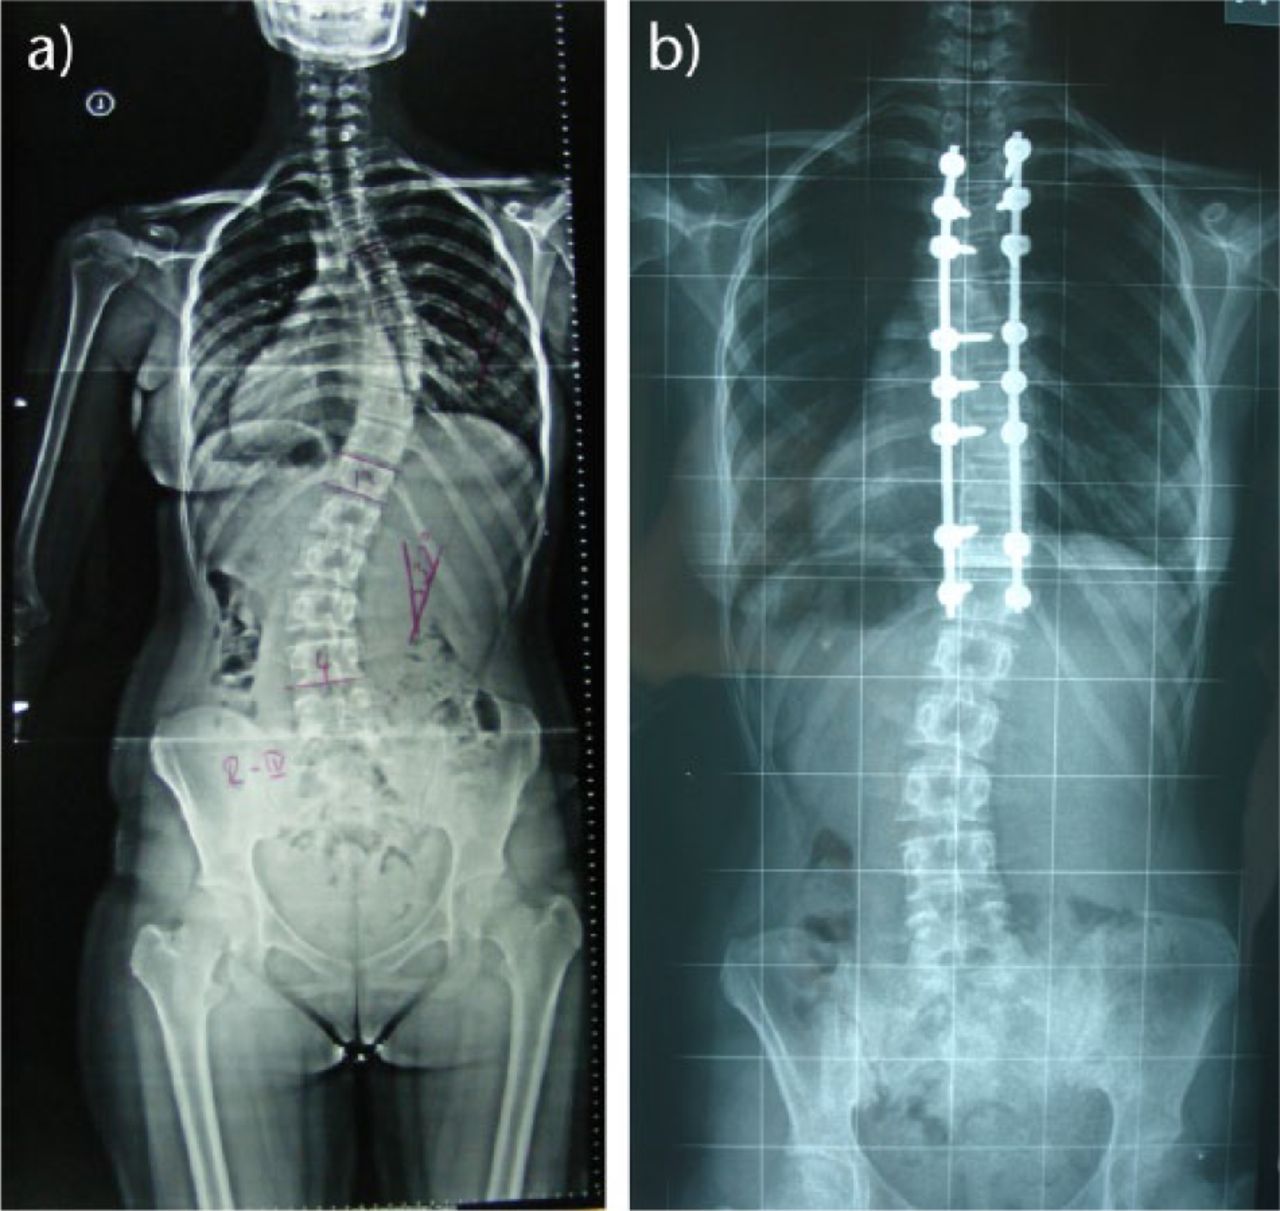

SPINE DEFORMITY CORRECTION

Spine deformity correction refers to surgery to correct deformed spine structures due to a number of different conditions. These can include both scoliosis and kyphosis, though the underlying cause of these conditions can range from defects not corrected at birth to injury, trauma and accidents. Deformity correct straightens curved sections of the spine and fuses the vertebrae to ensure further movement does not occur.